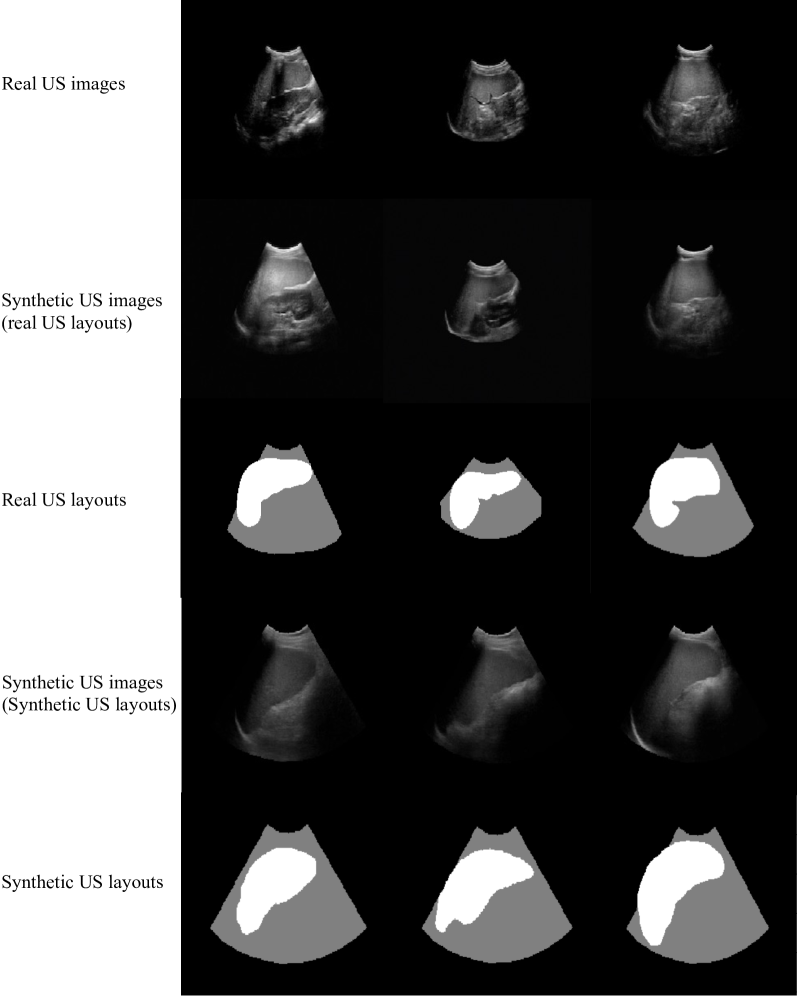

5.2.2 Synthetic US Generation

We performed inference using the USDM and the US layouts produced from the CT-derived segmentations and also from real US images. Fig. 13 illustrates the original US images alongside the corresponding synthetic US images and also the synthetic US layouts and corresponding synthetic US images. It can be seen from Fig. 13 that the synthetic US images generated from real US layouts have strong similarity to the real US images. The USDM can simulate the tissues and structures surrounding the spleen as well as the artefacts. The synthetic US images generated from manually created US layouts also show high fidelity and realism.

Refer to caption

Fig. 13: Examples of real US images, synthetic US images generated from real US layouts, and the corresponding real US layouts. Below are shown synthetic US images and the corresponding synthetic US layouts, which were manually created based on 2D CT spleen segmentations.

To quantitatively evaluate the similarity between the real US images and the synthetic US images generated from real US layouts, we computed the average structural similarity index (SSIM) between corresponding synthetic/real images, which was 0.7982, and the peak signal-to-noise ratio (PSNR), which was 20.98 dB. We also assessed the distributional similarity in deep feature space using the Kernel Inception Distance (KID), which was calculated as 0.0685±0.0031plus-or-minus0.06850.00310.0685\pm 0.00310.0685 ± 0.0031. Additionally, to demonstrate its applicability in clinical tasks, we evaluated the performance of a downstream spleen segmentation task. As reported in Table 4, the Dice coefficient was 0.9285 for real US images and 0.9624 for synthetic US images generated from real layouts.